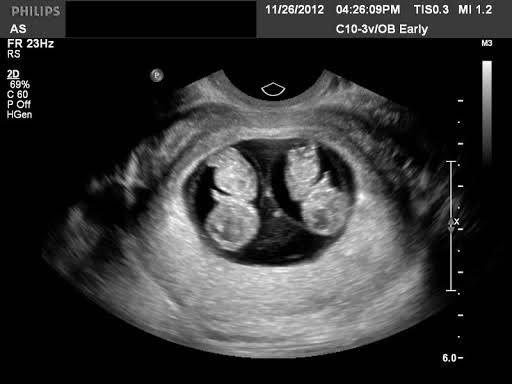

"Đi gặp 2 bé con nhỏ trong bụng em bé này" vừa nói hắn vừa xoa xoa cái bụng của anh vì anh mang thai đôi nên bụng anh đã to hơn người mang thai đơn bình thường.Anh nghe hắn nói vậy thì hạnh phúc lắm chủ động thơm lên má hắn 1 cái rồi cùng hắn đi ăn tối uống sữa để ngày mai còn đi gặp 2 bé con của mình nữa

Trong phòng siêu âm là âm thanh nhịp tim của 2 bé con đang đập rất mãnh liệt có lẽ 2 bé con biết rằng anh đang buồn nên 2 bé đang cố làm cho anh vui. Đột nhiên bác Phúc cười lớn rồi nói "là 2 cậu hoàng tử đấy nhé". Anh nghe thấy giới tính của con thì hạnh phúc lắm nhưng sẽ hạnh phúc hơn khi hắn cũng ở đây nghe giới tính của con và cả nhịp tim nữa nhưng có lẽ điều đó là quá xa vời với anh hiện tại rồi. Ở thời điểm này anh biết cuộc sống của anh sẽ trở về quỹ đạo cũ và rất có thể nó sẽ rất tệ.